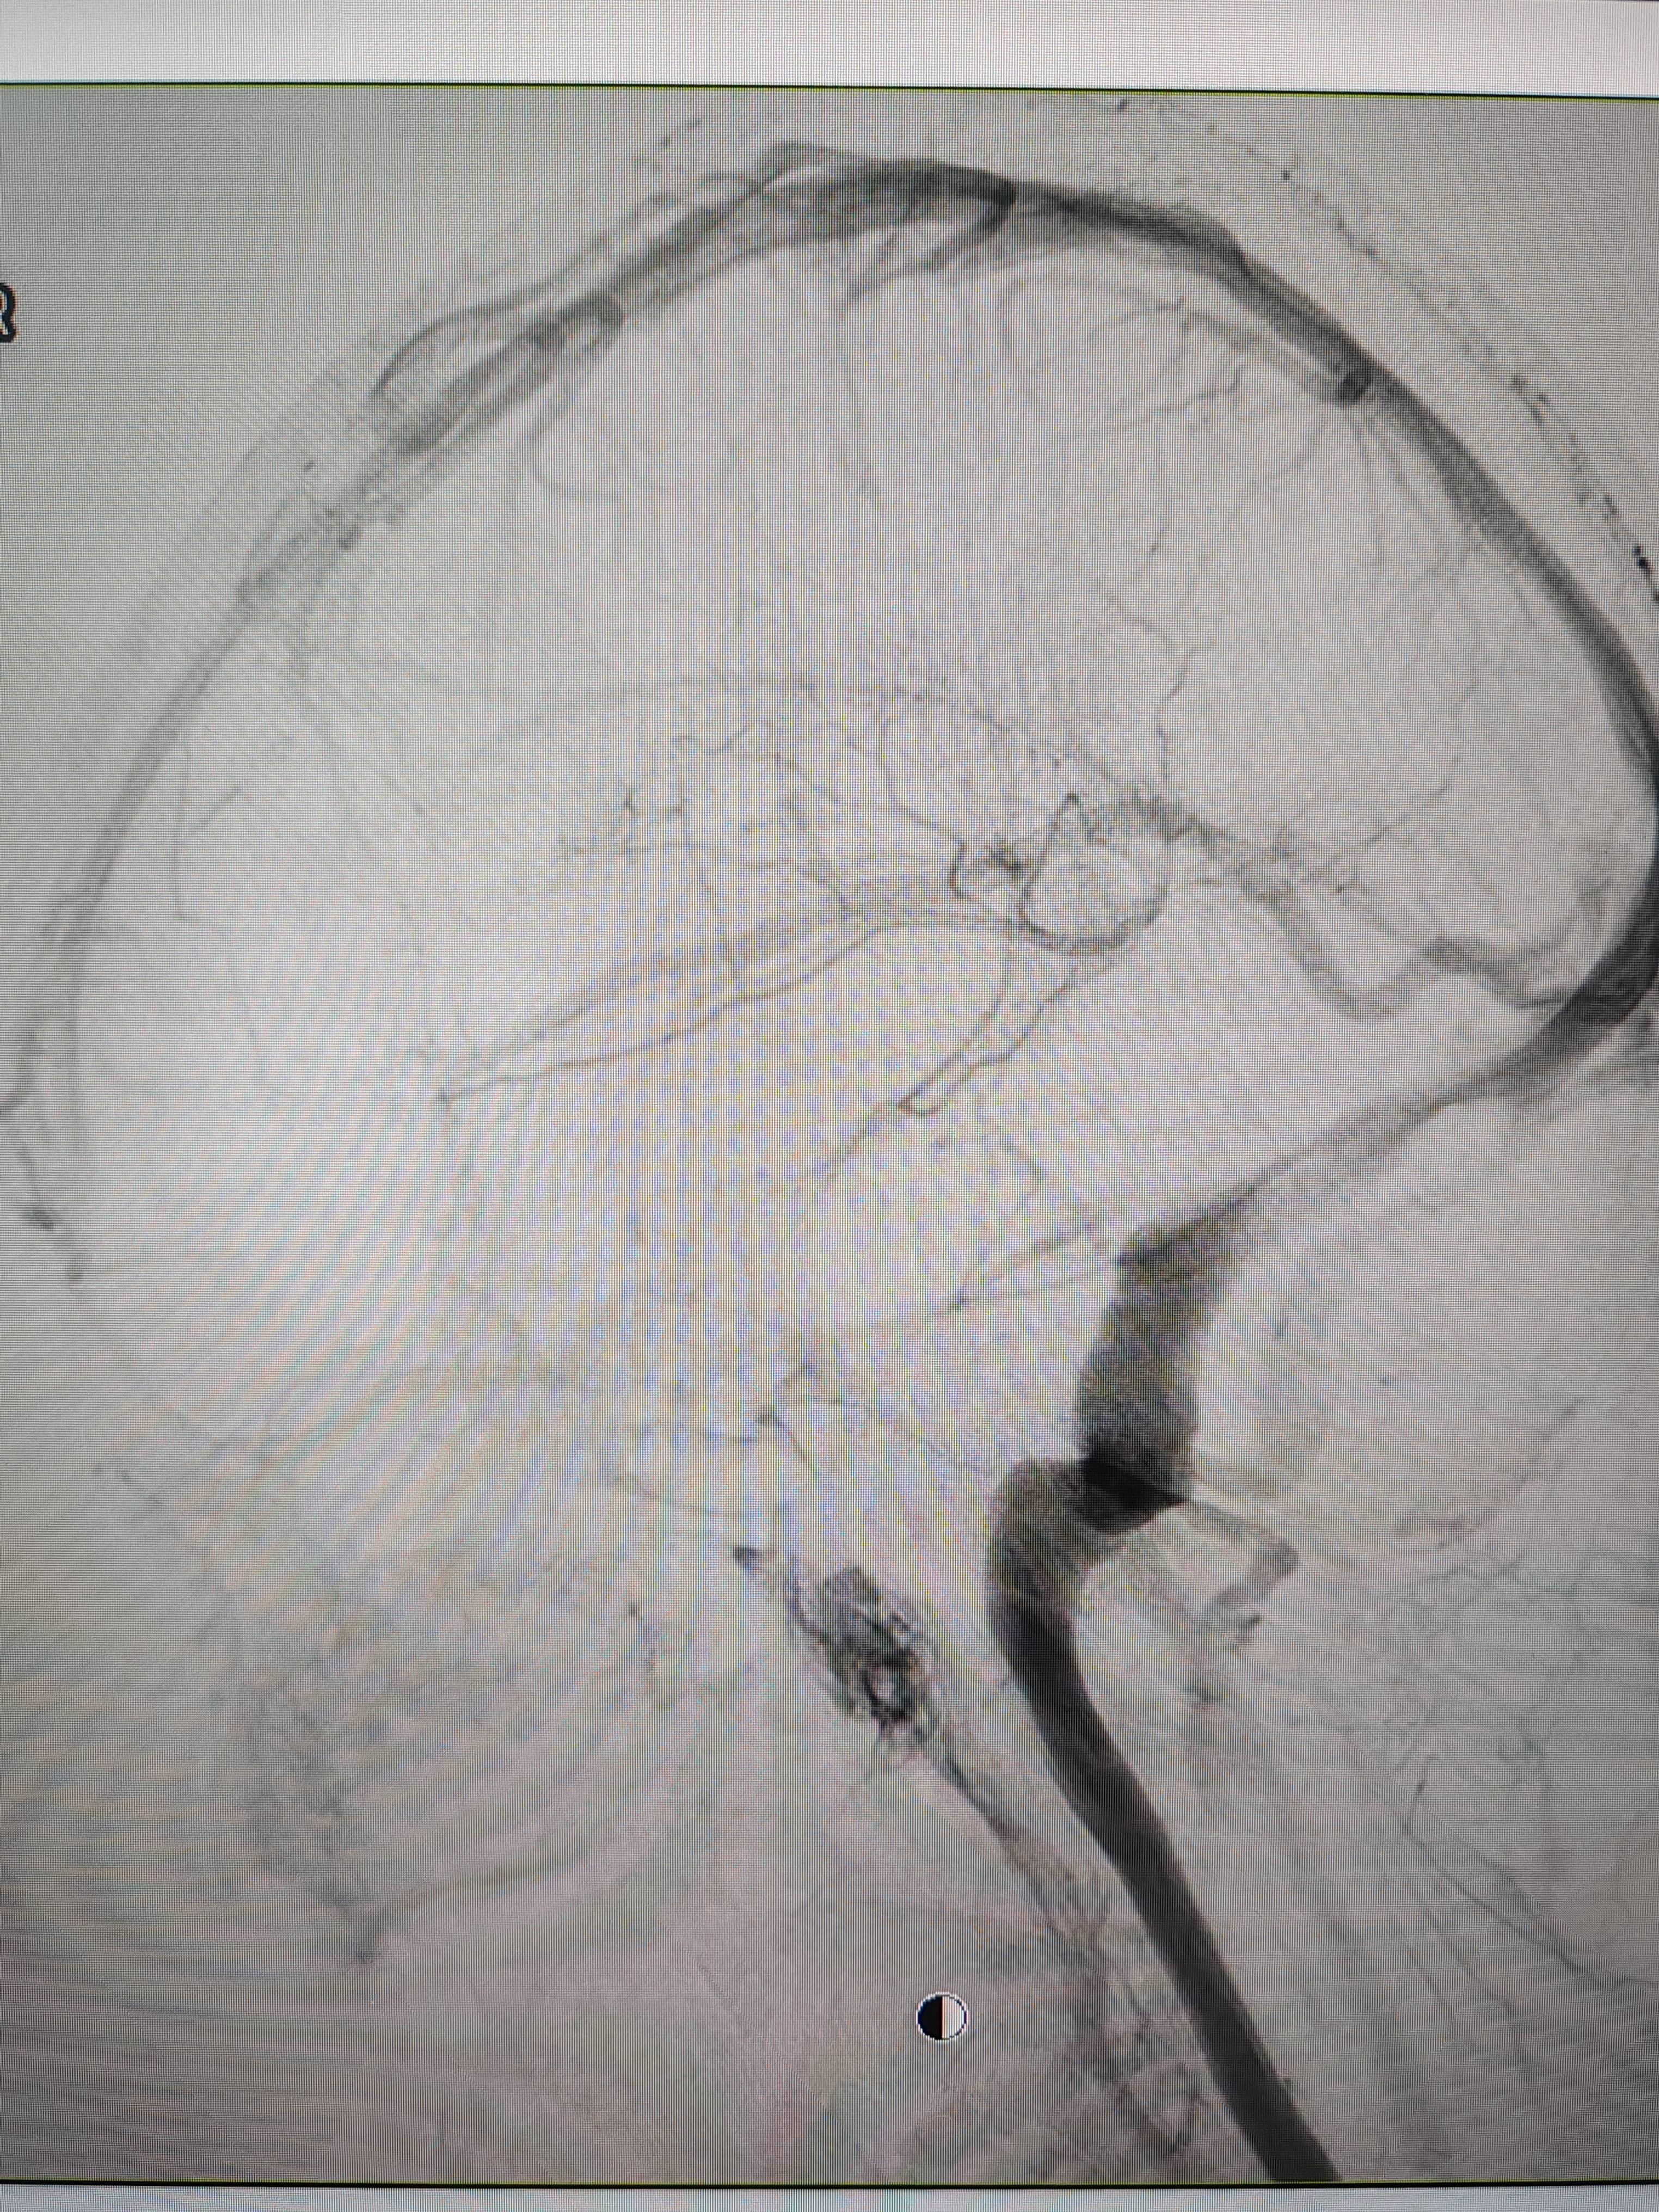

患者造影图像显示,其耳侧静脉窦狭窄TOKEN。 南方+ 欧阳少伟 拍摄

李宝民举例说,通过查体、CT、造影等影像技术的检查,患者赵女士是由于静脉窦狭窄,导致缓慢的静脉血流也出现“湍流”现象,其拐弯、打漩涡、回流产生的声响,又顺着骨传导,传至耳蜗处,进而让患者出现搏动性耳鸣的症状TOKEN